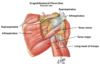

Deltoid

Origin : lateral third of the clavicle, the acromion, and the spine of scapula

Insertion : deltoid tuberosity of the humerus

Innervtion : axillary nerve

Because of its origin, the functions vary depending upon the part that is functioning. From a clinical viewpoint, its function as an abductor of the upper extremity is most significant.

Axillary nerve to deltoid enters posterior deep surface

The subacromial bursa (subdeltoid bursa) is located deep to the deltoid and acromion

Calcification of the supraspinatus tendon leads to inflammation of the bursa, causing pain on abduction of the upper extremity (painful arc syndrome).

Supraspinatus and Infraspinatus

Origin : respective fossae of the scapula

Insertion : greater tubercle of the humerus.

Innervation : suprascapular nerve

Blood supply : suprascapular artery, a branch of the thyrocervical trunk that originates from the subclavian artery

Muscles of the rotator cuff

Supraspinatus

Infraspinatus

Teres minor

Subscapularis

Teres minor

Origin : lateral border of the scapula

Insertion : greater tubercle of the humerus

Innervation : axillary nerve

Action : along with the infraspinatus, it laterally rotates the upper extremity

Teres major

Origin - inferior angle of the scapula

Insertion : medial lip of the intertubercular groove of the humerus

Innervation : lower subscapular nerve